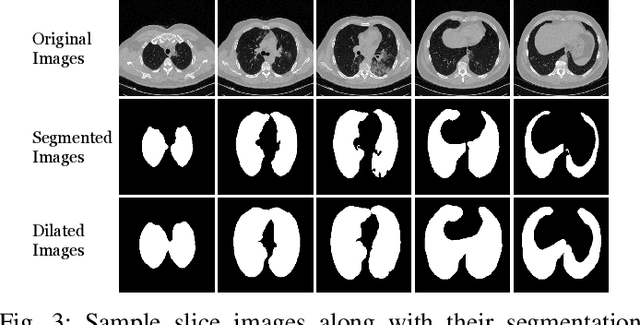

Abstract:Detecting COVID-19 in computed tomography (CT) or radiography images has been proposed as a supplement to the definitive RT-PCR test. We present a deep learning ensemble for detecting COVID-19 infection, combining slice-based (2D) and volume-based (3D) approaches. The 2D system detects the infection on each CT slice independently, combining them to obtain the patient-level decision via different methods (averaging and long-short term memory networks). The 3D system takes the whole CT volume to arrive to the patient-level decision in one step. A new high resolution chest CT scan dataset, called the IST-C dataset, is also collected in this work. The proposed ensemble, called IST-CovNet, obtains 90.80% accuracy and 0.95 AUC score overall on the IST-C dataset in detecting COVID-19 among normal controls and other types of lung pathologies; and 93.69% accuracy and 0.99 AUC score on the publicly available MosMed dataset that consists of COVID-19 scans and normal controls only. The system is deployed at Istanbul University Cerrahpasa School of Medicine.